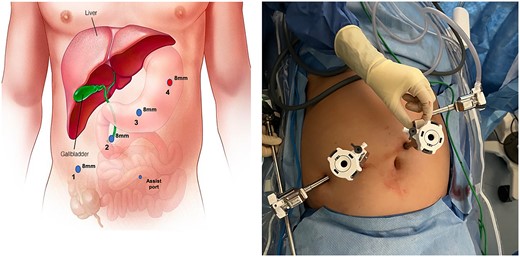

After anesthesia induction, indocyanine green 2.5 mg was administered. A Veress needle was used for entry, and four 8-mm trocars were inserted in her left mid-abdomen, two centrally and one in the right mid-abdomen (Fig. 3). An adherent small bowel loop was sharply dissected off the anterior abdominal wall. A small serosal injury was oversewn robotically with an interrupted 2-0 Vicryl suture after docking the DaVinci robot. The gallbladder was carefully separated from the adherent duodenum, and an approximately 1-cm fistula was noted (Fig. 4). The duodenotomy was repaired in two layers with an inner full thickness and an outer interrupted submucosal layer using absorbable suture (Fig. 5). Next, using FireFly to confirm biliary anatomy, the chronically inflamed gallbladder was dissected off the adherent common bile duct and right hepatic duct. After the critical view of safety was achieved, the cystic artery and duct were robotically clipped and transected. The intrahepatic gallbladder was dissected off the cystic plate, and a 10-French drain was left in the gallbladder fossa.

Trocar placement. Veress entry was performed at Palmer's point. Three additional 8-mm ports were placed approximately 6-cm equidistant as shown. The Veress entry site is increased in size to accommodate the #4 8-mm trocar. Instrumentation is as follows: 1) fenestrated bipolar 2) robotic camera 3) interchangeable port (monopolar scissor, robotic suction, prograsp) 4) tip-up with 4x4 inserted to elevate the liver 5) 5 mm assist port if needed.